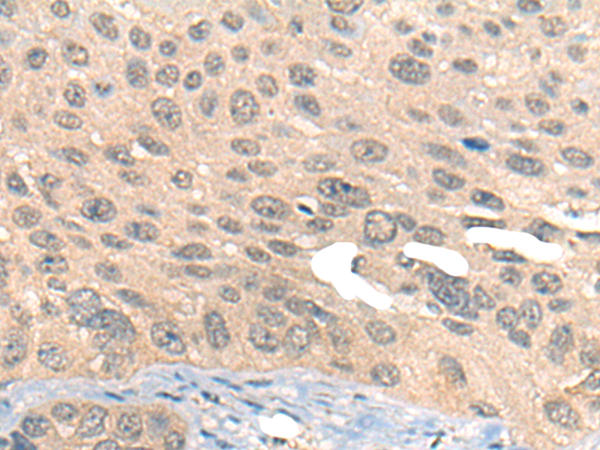

IHC positive control:

Human ovarian cancer

IHC Recommend dilution:

20-100